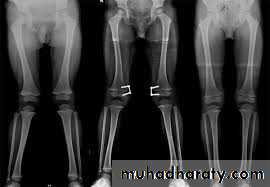

Deformities of the knee joint

In normal adult the knee are in 5-7 degree valgus ; any deviation from this may regarded as deformity .

The three common deformities are :

1- bow leg deformity (genu varum) .

2- knock knee (genu valgum) .

3- hyper extension(genu recurvatum) .

Bow legs & knock knee

in babies are so common that are consider to be normal stage of development (physiological) ; in addition to this , rickets may play a role in developing these deformities physiological or renal rickets .

Bilateral bow leg

Measurement :

: distance between the femoral condyles with the legs held in full extension , and the heel touching ; it should be

less than 6 cm .

Knock knee

The distance between the medial malleoli when the knee are held touching; it is usually

less than 8 cm .